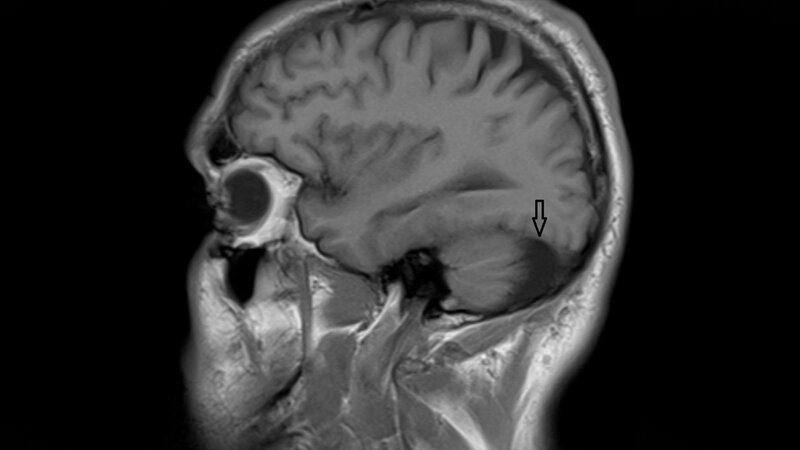

Arachnoidalzysten stellen etwa 1 % der intrakraniellen Raumforderungen dar. Der Mechanismus der Zystenvergrößerung wird kontrovers diskutiert. Der Gehalt an Proteinen der Arachnoidalzysten und des zerebrospinalen Liquors erscheint relativ ähnlich, doch gibt es eine bestimmte Anzahl an Proteinen, die sich signifikant unterscheiden. Das kann auf eine Veränderung der Proteine durch den Füllmechanismus oder auf eine Wirkung der Zystenmembran zurückzuführen sein. Bei Patienten mit Cluster-Kopfschmerz sollte eine KM-assistierte MRT bei normaler neurologischer Untersuchung erfolgen.

Arachnoid cysts are common, accounting for approximately 1 % of intracranial mass lesions. The mechanism of enlargement of arachnoid cysts is controversial. The protein content of arachnoid cyst fluid and cerebrospinal fluid appears to be similar. There are proteins that were significantly differentially abundant between arachnoid cyst fluid and cerebrospinal fluid. This could reflect the possibility that these proteins are affected by the filling mechanism of arachnoid cysts or are shed from the membranes into arachnoid cyst fluid. Neuroimaging, preferably contrast-enhanced magnetic resonance imaging should always be considered in patients with cluster headache despite normal neurological examination.